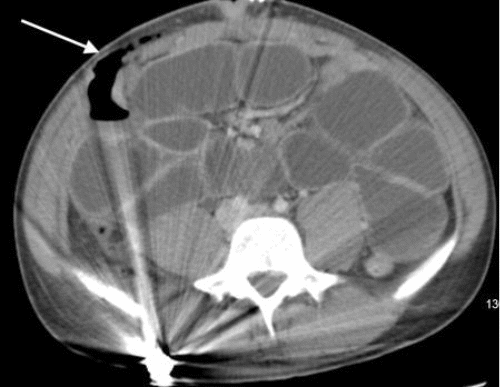

Contrast-enhanced CT scan of the abdomen and pelvis revealed findings consistent with mechanical obstruction. A transition point abutting the abdominal wall at the prior projectile injury site was noted proximal to the ileocolic anastomosis (Figure 3). A small bowel follow-through demonstrated small amounts of contrast in the distal small bowel loops at an 8-hour delay, indicating possible incomplete obstruction (Figure 4). Following discussion with the patient and guardian, a decision was made to perform a re-exploratory laparotomy.

Figure 3. CT Depicting Mechanical Small Bowel Obstruction at Prior Injury Site. Published with Permission

Axial view demonstrating the transition point abutting the fascial defect in the abdominal wall

(B) Axial view showing the collapsed bowel originating proximal to the ileocolic anastomosis (blue arrow)

(C) Axial view  of the ileocolic anastomosis (green arrow)